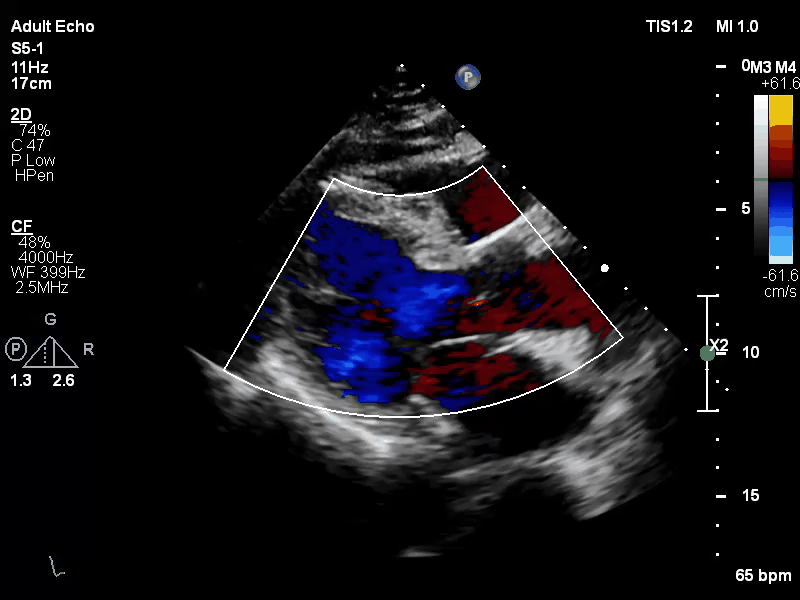

基本情况:老年男性,因“间歇性心悸、气短、胸闷、胸痛7年、加重7天”入院。患者于7年前劳累后感心悸、气短、胸闷、胸痛,休息后缓解,近7天患者加重,至西京医院就诊,超声心动图提示:二尖瓣后瓣脱垂伴关闭不全;左房、左室扩大,右房大;彩色血流示,二尖瓣瓣上反流(极重度),主动脉反流(少量),三尖瓣反流(少量);LVEF 51%。经手术专家评估该患者外科手术风险高,且患者拒绝行外科手术。术前诊断:心脏瓣膜病,二尖瓣关闭不全(极重度),心脏扩大,心房纤颤,心功能III-IV级(NYHA分级)。

Carpentier II,DMR,二尖瓣P2区域腱索断裂导致极重度二尖瓣反流,心脏扩大,脱垂宽度较大,间隙约10mm,瓣口面积13cm²,2区前叶长42mm,后叶长21mm。反流束来自于2区,呈偏心性,沿前叶走行,EROA=1.06cm² (r=1.5cm, av=0.3cm/s, pv=4.0m/s),VC 1.2 cm。PGmean 3mmHg,TR 2+。房间隔穿刺空间约6cm。

手术于全麻下进行,采用股静脉房间隔途径,房间隔穿刺后置入外径22F导管鞘及夹合器输送系统,在TEE引导下,将1枚长宽型号的KoKaClip®夹合器顺利植入到二尖瓣A2/P2区,夹合器位置稳定。彩色多普勒超声显示微少量残余分流,整体反流量改善2级以上,肺静脉多普勒波形由反向恢复正常。多切面证实夹合组织充分,双孔化形成,遂移除器械输送系统,手术顺利完成。

术前

术后